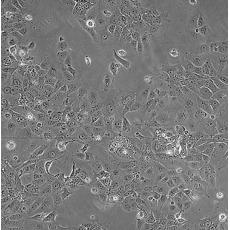

HCC827

產(chǎn)品名稱 HCC827

中文名稱 人非小細胞肺癌細胞

組織來源 肺腺癌;女性

生長特性 adherent

形態(tài)特征 epithelial

細胞描述 This lung adenocarcinoma has an acquired mutation in the EGFR tyrosine kinase domain(E746-A750 deletion).